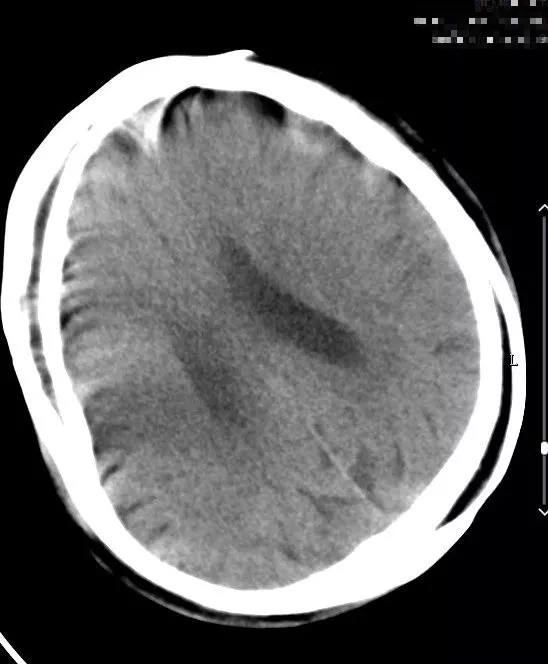

头颅CT(2018-08-03,本院)阅片未见出血。

入院时头颅CT(07:48分)

9:00患者诉头痛,查体:神清,精神可,言语清晰,左侧肢体肌力较前好转,左侧肢体肌力4级,右侧肢体肌力正常。急查头颅CT未见出血。患者CT检查时开始出现不配合检查。